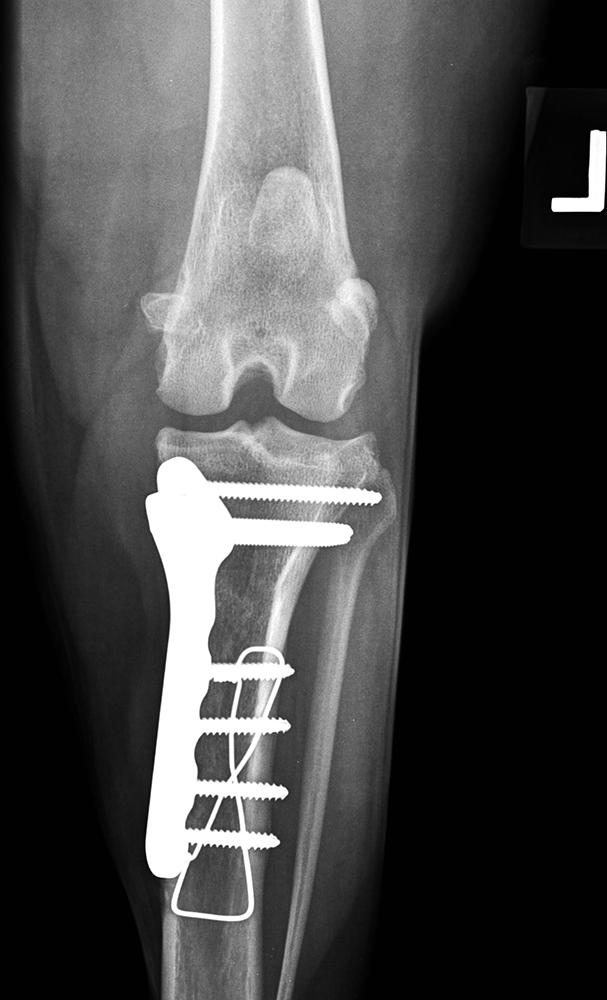

Caudocrâniale